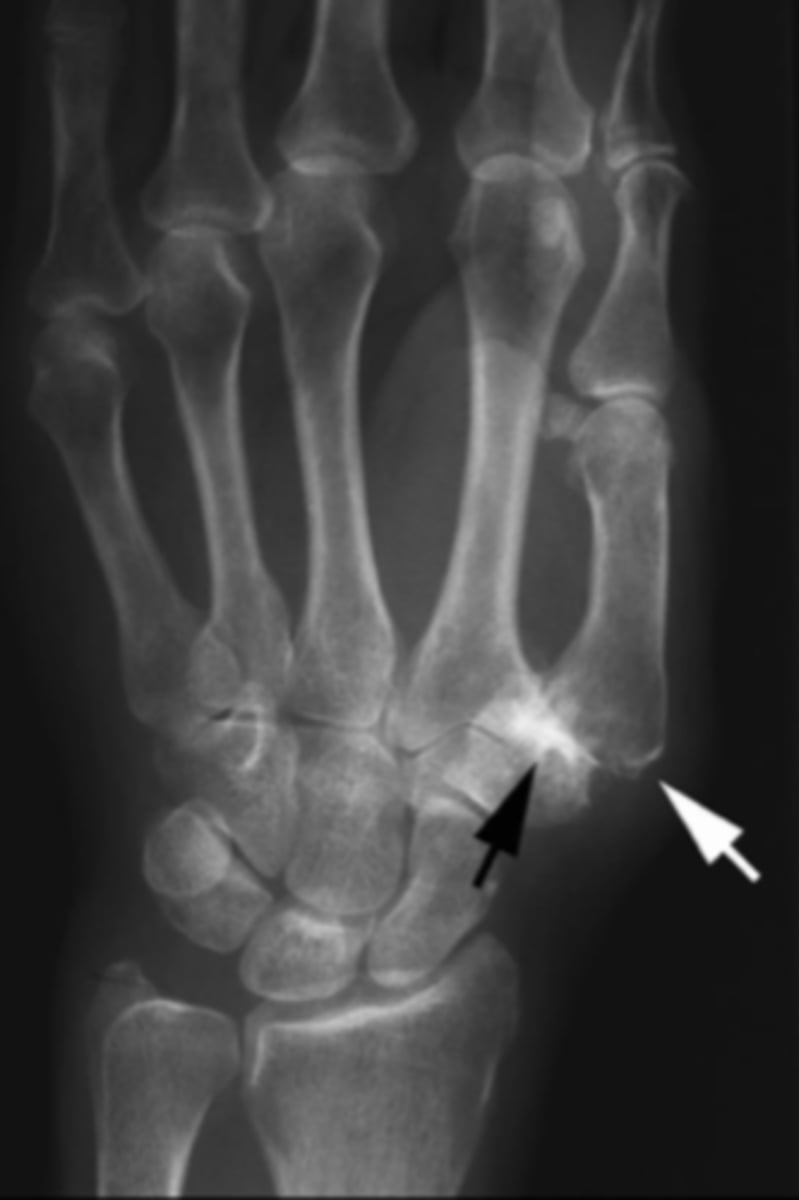

Terry Thomas sign (DISI)

What is the issue?

TFCC disorder